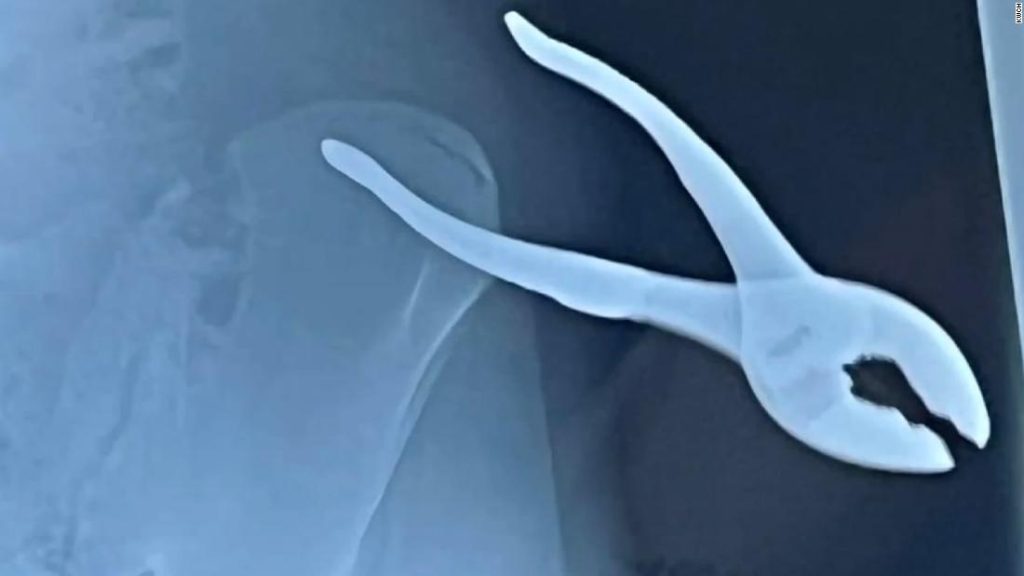

A Kansas teenager is recovering after a slip on some ice led to a freak accident. 15-year-old Joey Zeman was helping with snow removal when he fell, impaling himself on a pair of pliers. CNN affiliate KWCH reports.A Kansas teenager is recovering after a slip on some ice led to a freak accident. 15-year-old Joey Zeman was helping with snow removal when he fell, impaling himself on a pair of pliers. CNN affiliate KWCH reports.

Teen impaled by pliers after freak accident